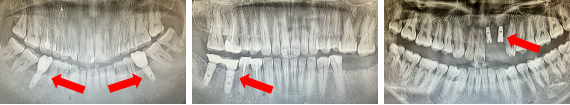

不同缺牙位点种植体X线影像